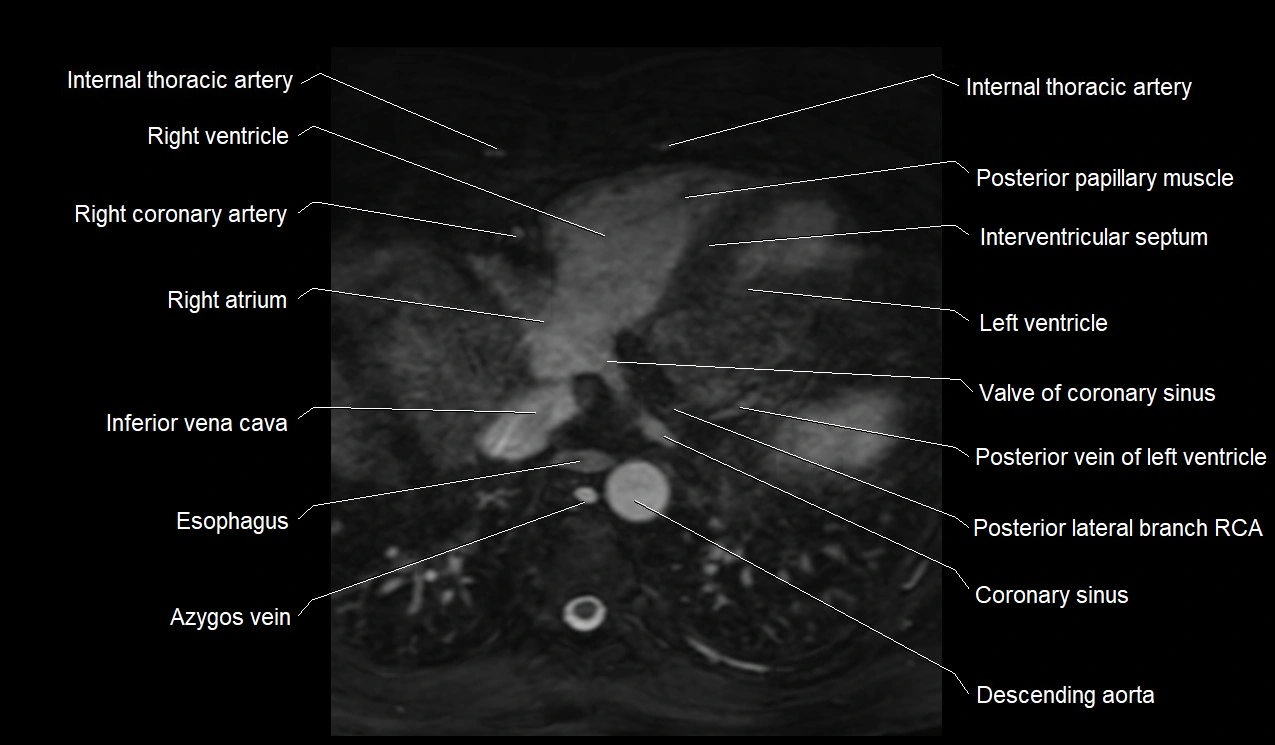

MRI image